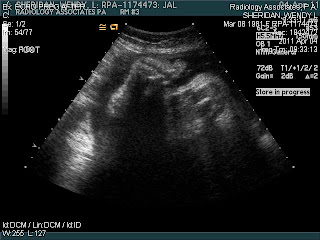

Finn at 35 weeks

I had an ultrasound on Monday morning to try and determine just how big Finn is these days. Dr. Harrison was surprised to say the least about how big this "little" guy is, HA! Right now, Finn is measuring at 38 weeks and is approxiamately 7lbs 5oz. With 5 more weeks to go and an average weight gain of 1/2 a pound a week, that would make Finn almost 10lbs by the time he's due. Dr. Harrison has agreed to induce me at 39 weeks, so unless Finn decides to come on his own before then it looks like we will have a baby by the end of the month. We are hopeful that he will come before then, without complications or having to have a c-section, but mostly we are just praying for a happy and most importantly healthy baby boy! And now on to the good stuff, pictures of our sweet guy....

Profile(Love those lips!)

Cute little foot

His sweet face, His cheeks are already nice and fat!

I can't wait to have him in my arms and kiss his sweet face. I'm so excited to see who he looks like!!!